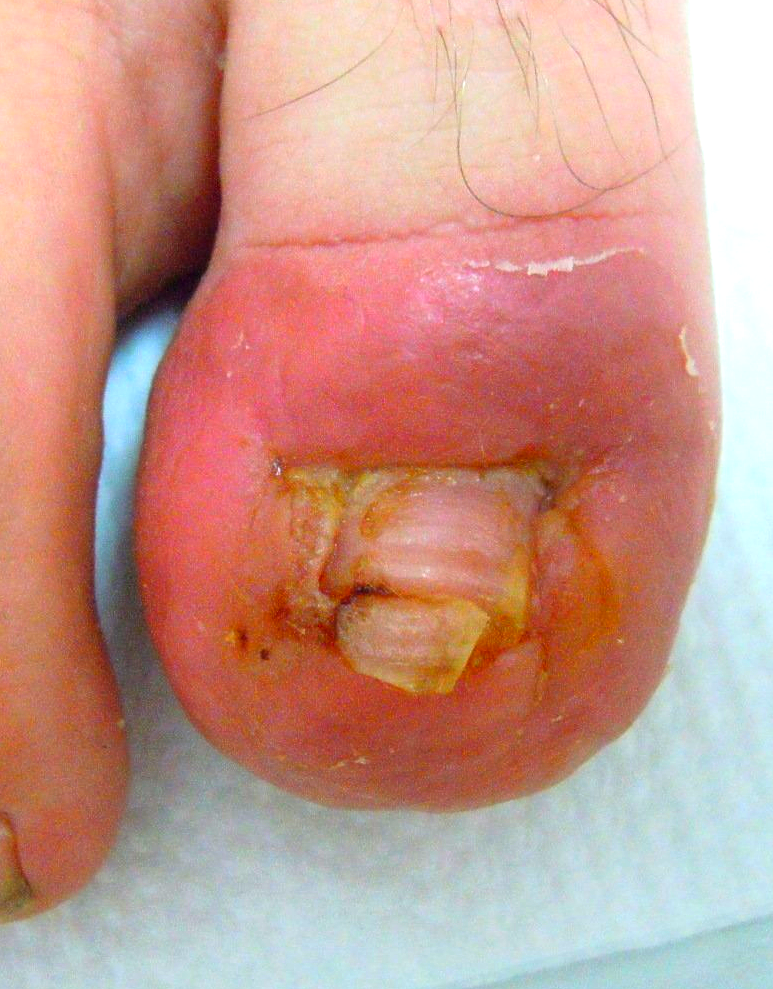

Hühnerauge subungual (unter der Nagelplatte)

Bild 1

die Ausgangssituation,

Bild 2

die geöffnete Nagelplatte unmittelbar nach der Entfernung des Hühnerauges

Bild 3

die wieder funktionell und ästhetisch verschlossene Nagelplatte (nach abgeschlossenem Heilungsverlauf)